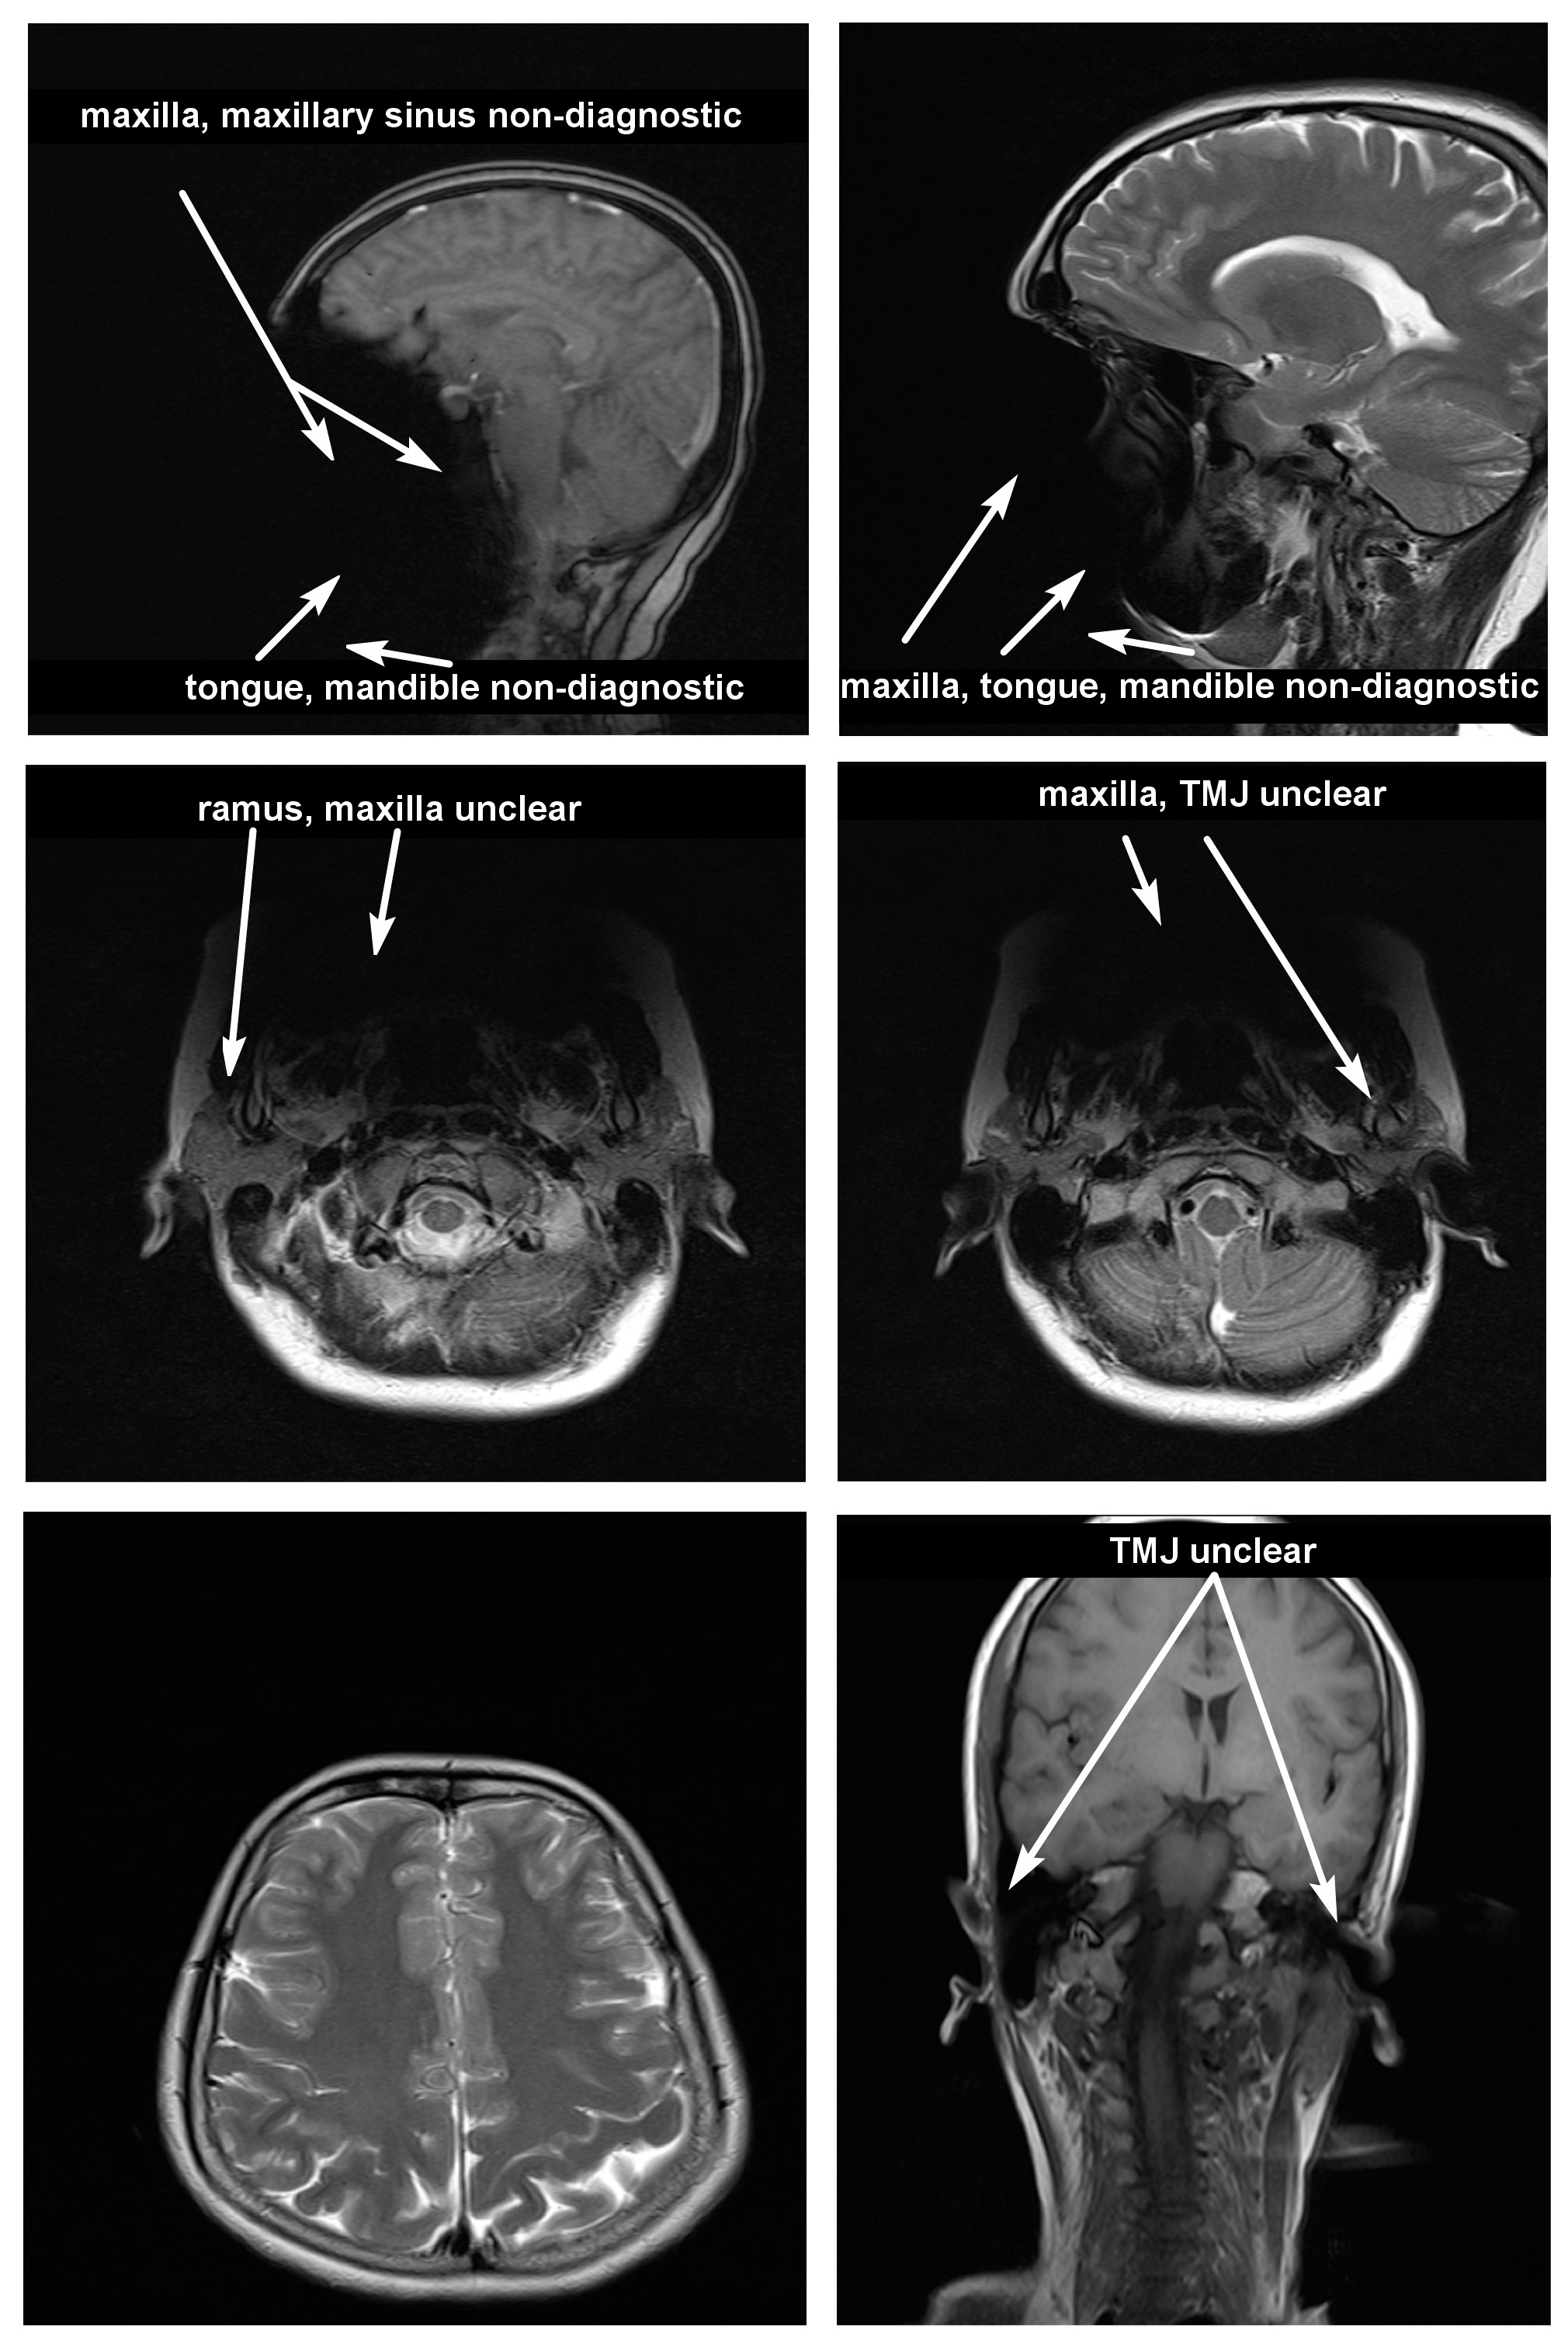

Magnetic resonance imaging scans were taken for all 38 subjects to study diagnostic image quality. Since the orthodontic appliances were securely bonded with orthodontic composite, there were no special precautions taken regarding the possible dislodgement and heating of the appliances, as previous studies had found changes in the temperature of the appliances to be clinically insignificant (within 1°C).16 The MRI scans for all types of bracket and retainer materials are shown in Figure 1, Figure 2, Figure 3, Figure 4, Figure 5, Figure 6, Figure 7, Figure 8, Figure 9, Figure 10. Non-diagnostic or unclear ROI are marked with arrows. None of the patients reported any discomfort or pain during MRI examination. The MRI scans were analyzed by a panel of 6 qualified and licensed radiologists, who assessed their diagnostic quality. The scans were compared with controls that included images from the archives of the Department of Radio-Diagnosis of Kamineni Institute of Medical Sciences. The radiologists ranked the images according to the distortion observed in the abovementioned ROI, using the modified receiver operating characteristic (ROC) analysis of distortion scoring system (Table 2), as described by Elison et al.17 In this method of distortion classification, a score of 3 represents the cut-off point for clinical usability. Images with a score of 3 have moderate distortion or artifacts, but they can still be used for diagnosis.

Table 4 presents the mean distortion scores for particular bracket and retainer materials based on the scores obtained for each subject. Each subject received a mean distortion score above 3 for stainless steel buccal and lingual brackets, indicating that the images were non-diagnostic. Each subject received a mean distortion score below 3 for other bracket and retainer materials, which indicates that these MR images were diagnostic.

Table 5 details the mean distortion scores obtained for different types of brackets and retainers according to the anatomic sites for all subjects. All sequences and all radiologists were considered when determining these mean values. Except for stainless steel buccal/labial and lingual brackets, other materials had an average distortion score below 3 with regard to various anatomic sites, indicating that these MR images were diagnostic. For stainless steel buccal/labial and lingual brackets, the mean distortion scores were above 3 consistently for each anatomic site except for the posterior cerebral fossa (a score of 1.16). This indicates that these MR images were non-diagnostic for all areas except for the posterior cerebral fossa.

In the present study, stainless steel buccal/labial and lingual orthodontic brackets caused more distortion of cranial MR images and received higher distortion scores for all anatomic sites than other orthodontic bracket and retainer materials. The mean distortion score assigned by the radiologists to stainless steel appliances was 3.67. According to the anatomic landmarks, it was 4 by the same radiologists for TMJ, the tongue, the maxilla, the mandible, and the maxillary sinus, which means maximum distortion of the MR images. However, it was only 1.16 for the posterior cerebral fossa. This indicates that stainless steel buccal/labial and lingual brackets caused distortion that was most severe in the anatomic sites adjacent to them. The mean score of 1.16 for the posterior cerebral fossa means that there was almost no distortion, which shows a pattern of reduced artifacts with an increasing distance of the anatomic site from the brackets.

Since stainless steel buccal/labial and lingual brackets consistently had higher distortion scores, the MR images were considered non-diagnostic. The results of this study are similar to those obtained by Patel et al.,8 Elison et al.,17 Razdan and Rani,23 Beau et al.,24 Zhylich et al.,25 and Cassetta et al.26 However, they are contradictory to the research done by Sadowsky et al., since an older version of an MRI machine was used in their study.12